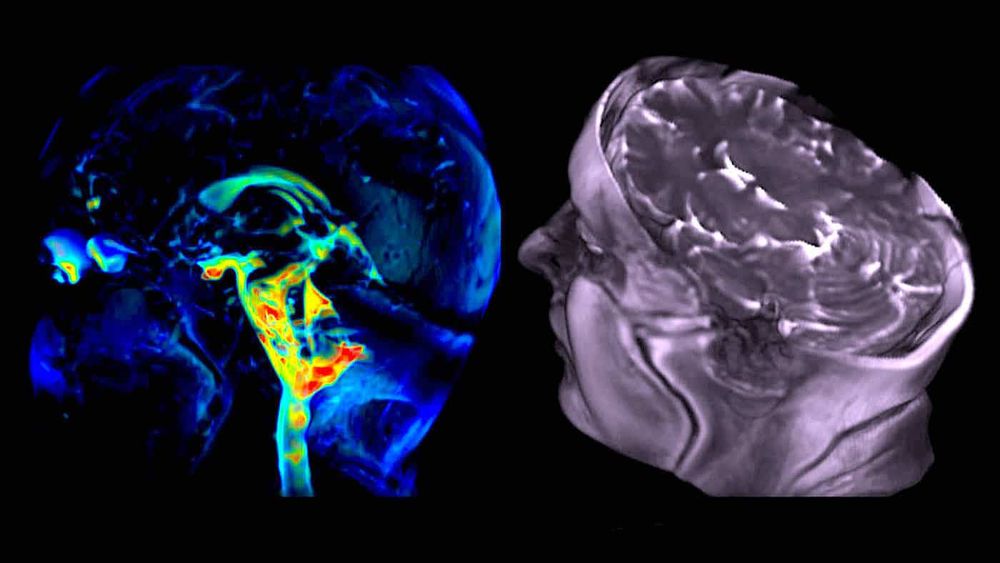

VIDÉO 1 : L'IRMa 3D permet non seulement d'obtenir un aperçu étonnant de l'intérieur du « cerveau qui pulse », mais aussi de mesurer ce mouvement physiologique dans toutes les directions. Ici, l'amplitude du mouvement du cerveau est superposée pour chaque tranche de cerveau et chaque orientation en 3D. [© 3D aMRI method outlined in Abderezaei et al. Brain Multiphysics (2021); Terem et al. Magnetic Resonance in Medicine (2021)] :

L'IRMa 3D du cerveau humain montre les mouvements infimes du cerveau à une résolution spatiale sans précédent de 1,2 mm³, soit environ la largeur d'un cheveu humain. Les mouvements réels sont amplifiés (rendus plus grands, jusqu'à 25 fois) pour permettre aux cliniciens et aux chercheurs de les visualiser en détail. Les détails frappants de ces mouvements animés et amplifiés pourraient aider à identifier des anomalies, telles que celles causées par des blocages des fluides rachidiens, qui comprennent le sang et le liquide céphalorachidien (LCR).